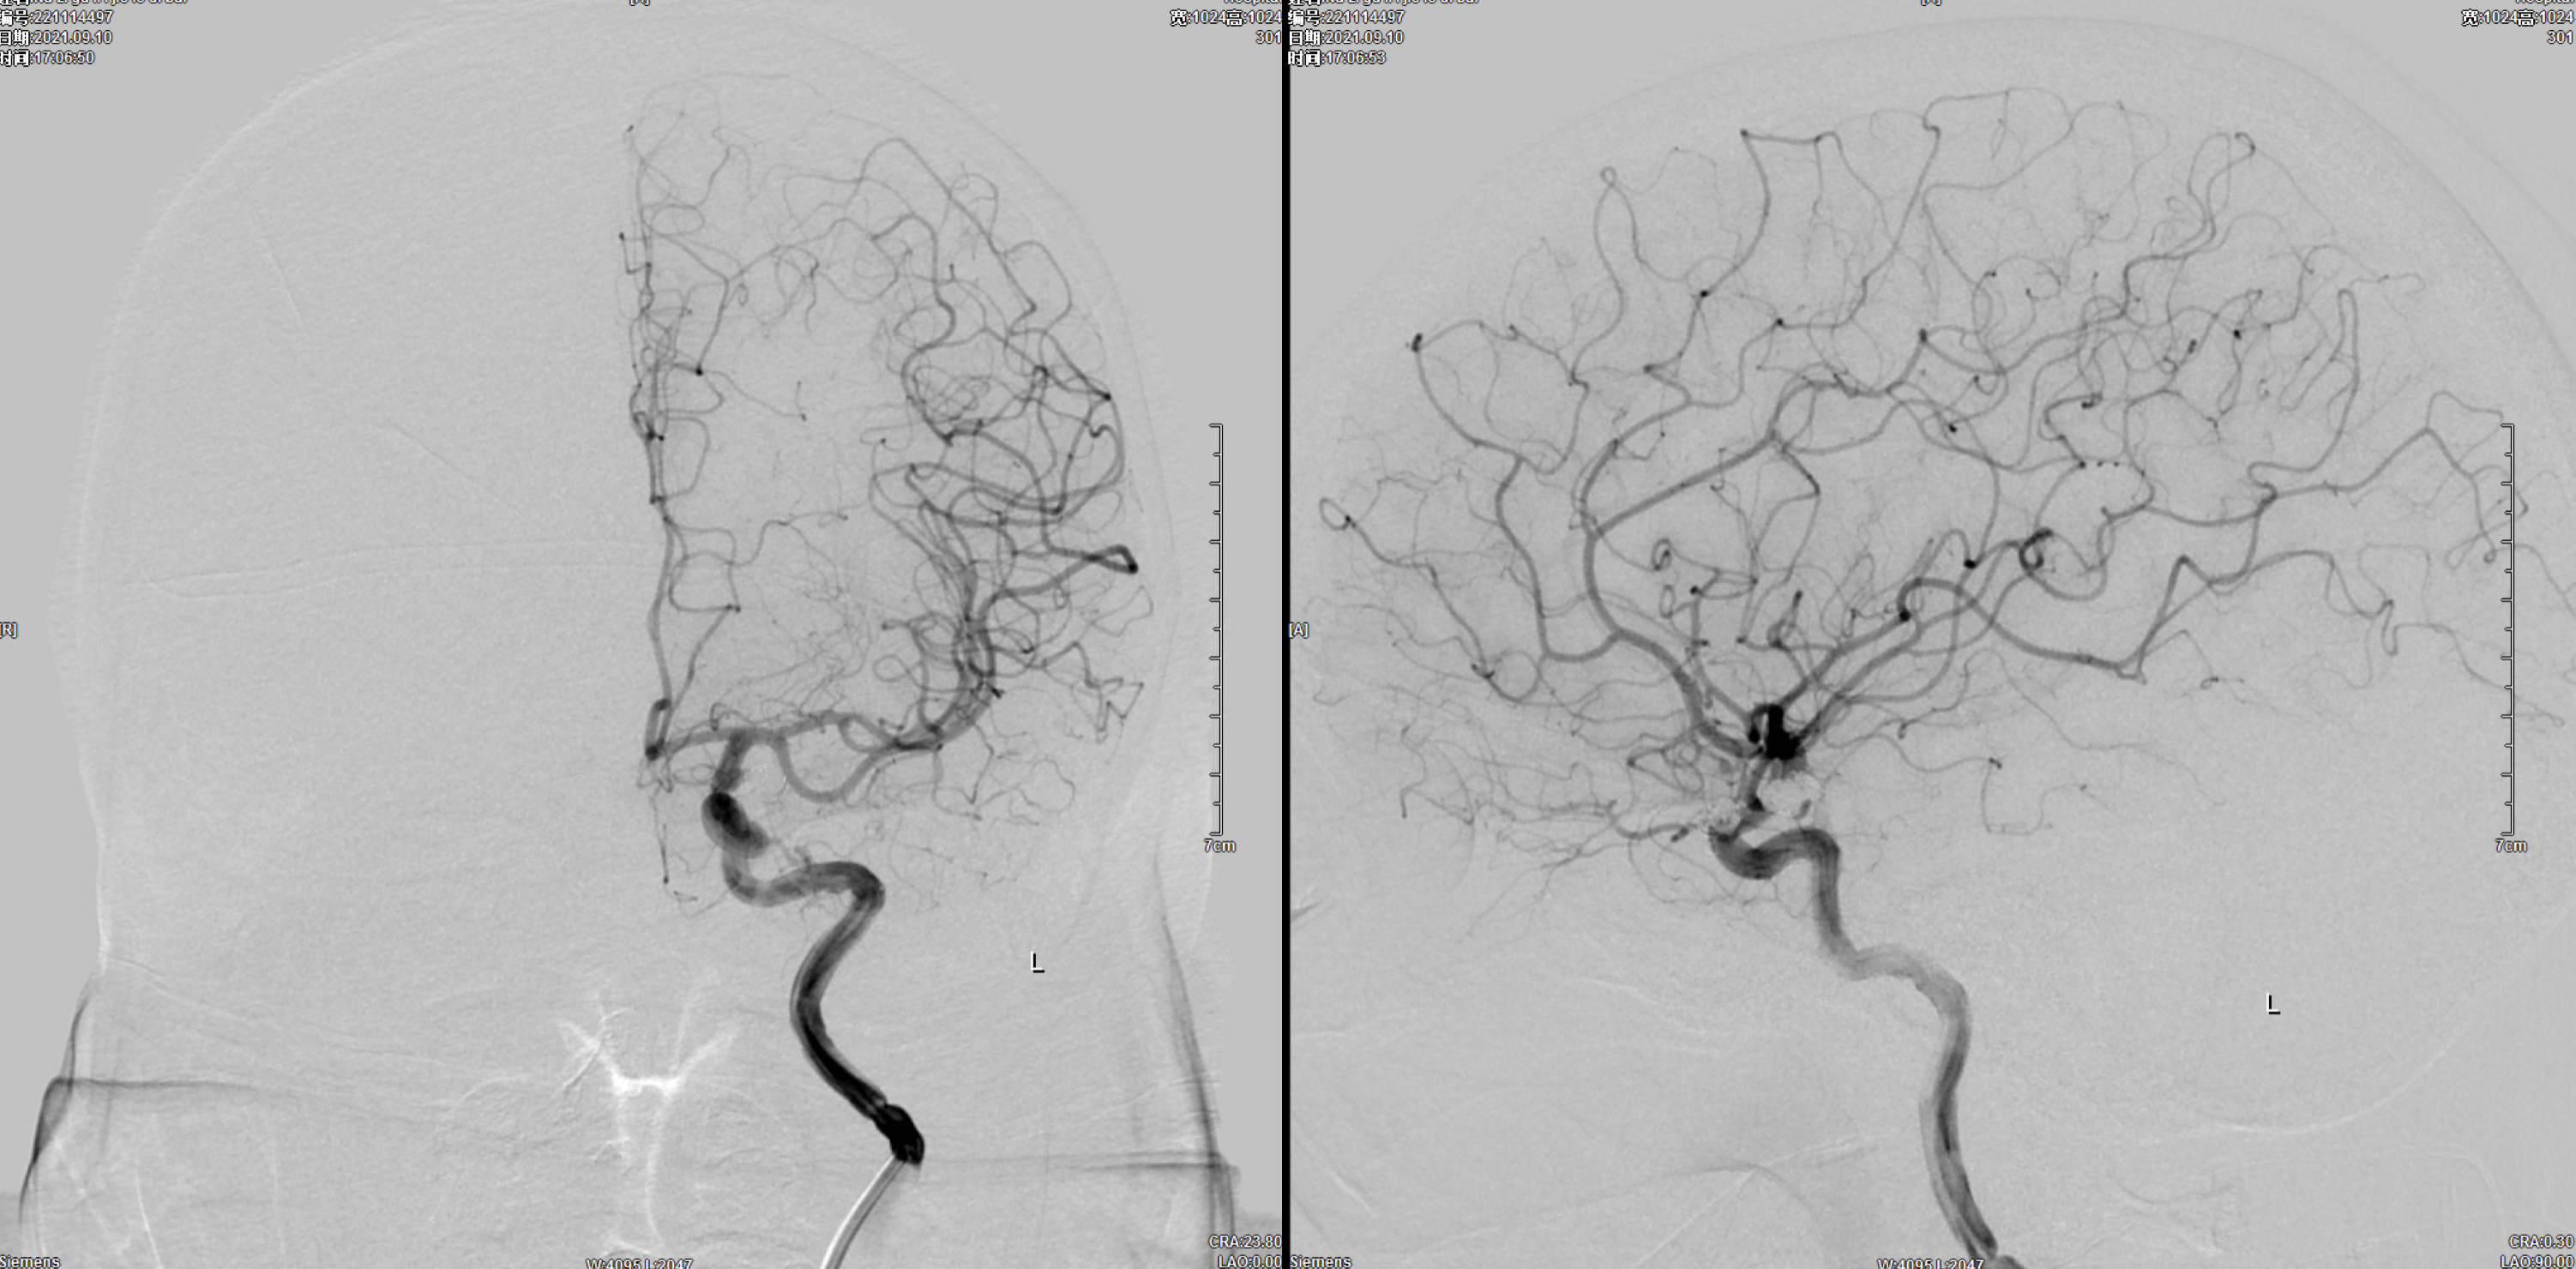

术后3月复查右侧颈内动脉正侧位造影:动脉瘤栓塞满意,未见残留及复发。

术后3月复查左侧颈内动脉正侧位造影:动脉瘤栓塞满意,未见残留及复发。